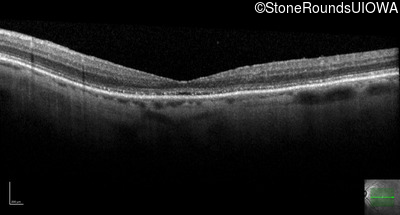

The clinical features favoring the diagnosis of RP1L1-associated occult macular dystrophy include: reduced acuity with a near-normal ophthalmoscopic appearance, a history of normal acuity in childhood; and, a "moth-eaten" appearance of the macular ellipsoid zone on OCT.

Age at visit: 79 years